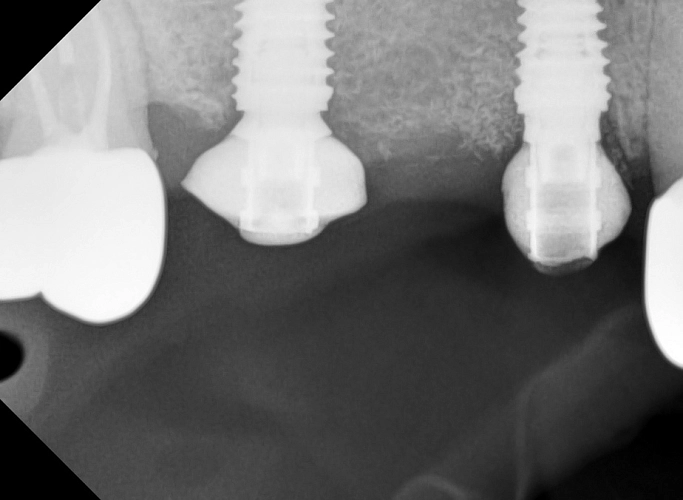

На фото проведена комплексная имплантация двух жевательных зубов стоматологом -хирургом Федотовым Р.В.